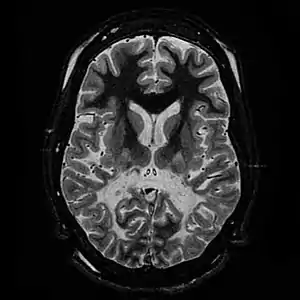

| T2 weighted axial scan of a human brain at the level of the caudate heads demonstrates marked loss of posterior white matter, with reduced volume and increased signal intensity. The anterior white matter is spared. Features are consistent with X-linked adrenoleukodystrophy. | |

When damage occurs to white matter, subsequent immune responses can lead to inflammation in the central nervous system (CNS), along with the loss of myelin. The degeneration of white matter can be seen in an MRI scan and is used to diagnose leukodystrophy. Leukodystrophy is characterized by specific symptoms, including decreased motor function, muscle rigidity, and eventual degeneration of sight and hearing. While the disease is fatal, the age of onset is a key factor, as infants have a typical life expectancy of 2–8 years, while adults typically live more than a decade after onset. Treatment options are limited, although hematopoietic stem cell transplantations using bone marrow or cord blood seem to help in certain leukodystrophy types, while further research is being done.

The degeneration of white matter, which reflects the degeneration of myelin, can be seen in a basic MRI and used to diagnose leukodystrophies of all types. T-1 and T-2 weighted fluid-attenuated inversion recovery (FLAIR) images are the most often used approach.[24] Electrophysiological and other kinds of laboratory testing can also be done. In particular, nerve conduction velocity is looked at to distinguish between leukodystrophy and other demyelinating diseases, as well as to distinguish between individual leukodystrophies. For example, individuals with X-ALD have normal conduction velocities, while those with Krabbe disease or metachromatic leukodystrophy have abnormalities in their conduction velocities.[24] Multigene sequencing panels for undifferentiated leukodystrophy are offered for rapid molecular diagnosis after genetic counselling.